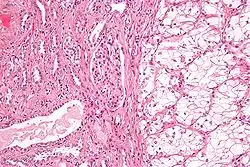

Microscopy

Generally, the cells have a clear cytoplasm, are surrounded by a distinct cell membrane and contain round and uniform nuclei.

Clear-cell renal-cell carcinoma. HE, × 100 -

Clear-cell renal-cell carcinoma. Fuhrman grade = 1. HE, × 400 -